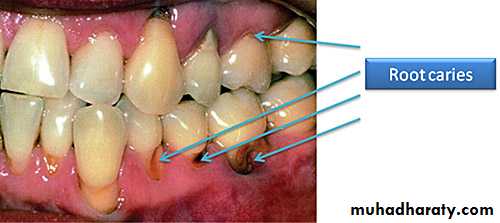

Root caries is a common problem among the elderly. Root caries, by definition, occurs on the root of the tooth. It is initiated on a root surface exposed to the oral environment.

Root caries can be defined as a soft irregularly shaped lesion either totally confined to the root surface or involved the enamel at the cemento- enamel junction but clinically indicating that the lesion is initiated on the root surface.

The most commonly used clinical signs to describe root caries utilized visual (color, contour, surface cavitation) ,

and tactile (surface texture) specifications. There are no reported clinical symptoms of root caries although pain may be present in advanced lesions.